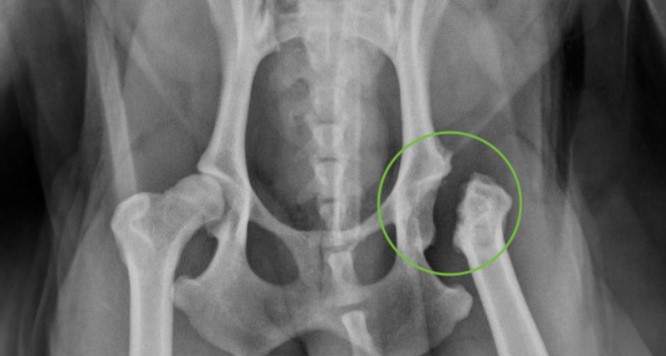

Остеоартрит, часто возникающий на фоне дисплазии тазобедренных суставов (фото 1) - это наиболее распространенная причина хромоты у собак всех возрастных групп. Для лечения собак с клиническими признаками хромоты, а также при первичных (нестабильность) или вторичных (остеоартрит) признаках дисплазии тазобедренных суставов применяются как консервативные методы терапии, так и хирургические вмешательства. К числу хирургических техник относятся тройная остеотомия таза, тотальное эндопротезирование тазобедренного сустава, остэктомия головки и шейки бедренной кости (фото 2). Последняя методика (по опубликованным данным) приводит к неудовлетворительным результатам по объективным и субъективным критериям примерно у 42% собак и кошек3.Предоперационное планирование

На основании неврологического осмотра не было выявлено патологических изменений. По результатам ортопедического осмотра правого и левого тазобедренных суставов: ограничение диапазона движений, крепитация, болезненность при манипуляциях; другие суставы без особенностей.Была проведена рентгенография тазобедренных суставов в дорсовентральной проекции с экстензией тазовых конечностей (фото 1).

Выявлены следующие патологические изменения правого и левого тазобедренных суставов:

- изменение формы головки бедренной кости;

- образование остеофитов на шейке бедренной кости;

- утолщение капсулы сустава (линия Моргана);

- покрытие головки менее 50%;

- сглаживание дорсального края вертлужной впадины;

- субхондральный склероз.